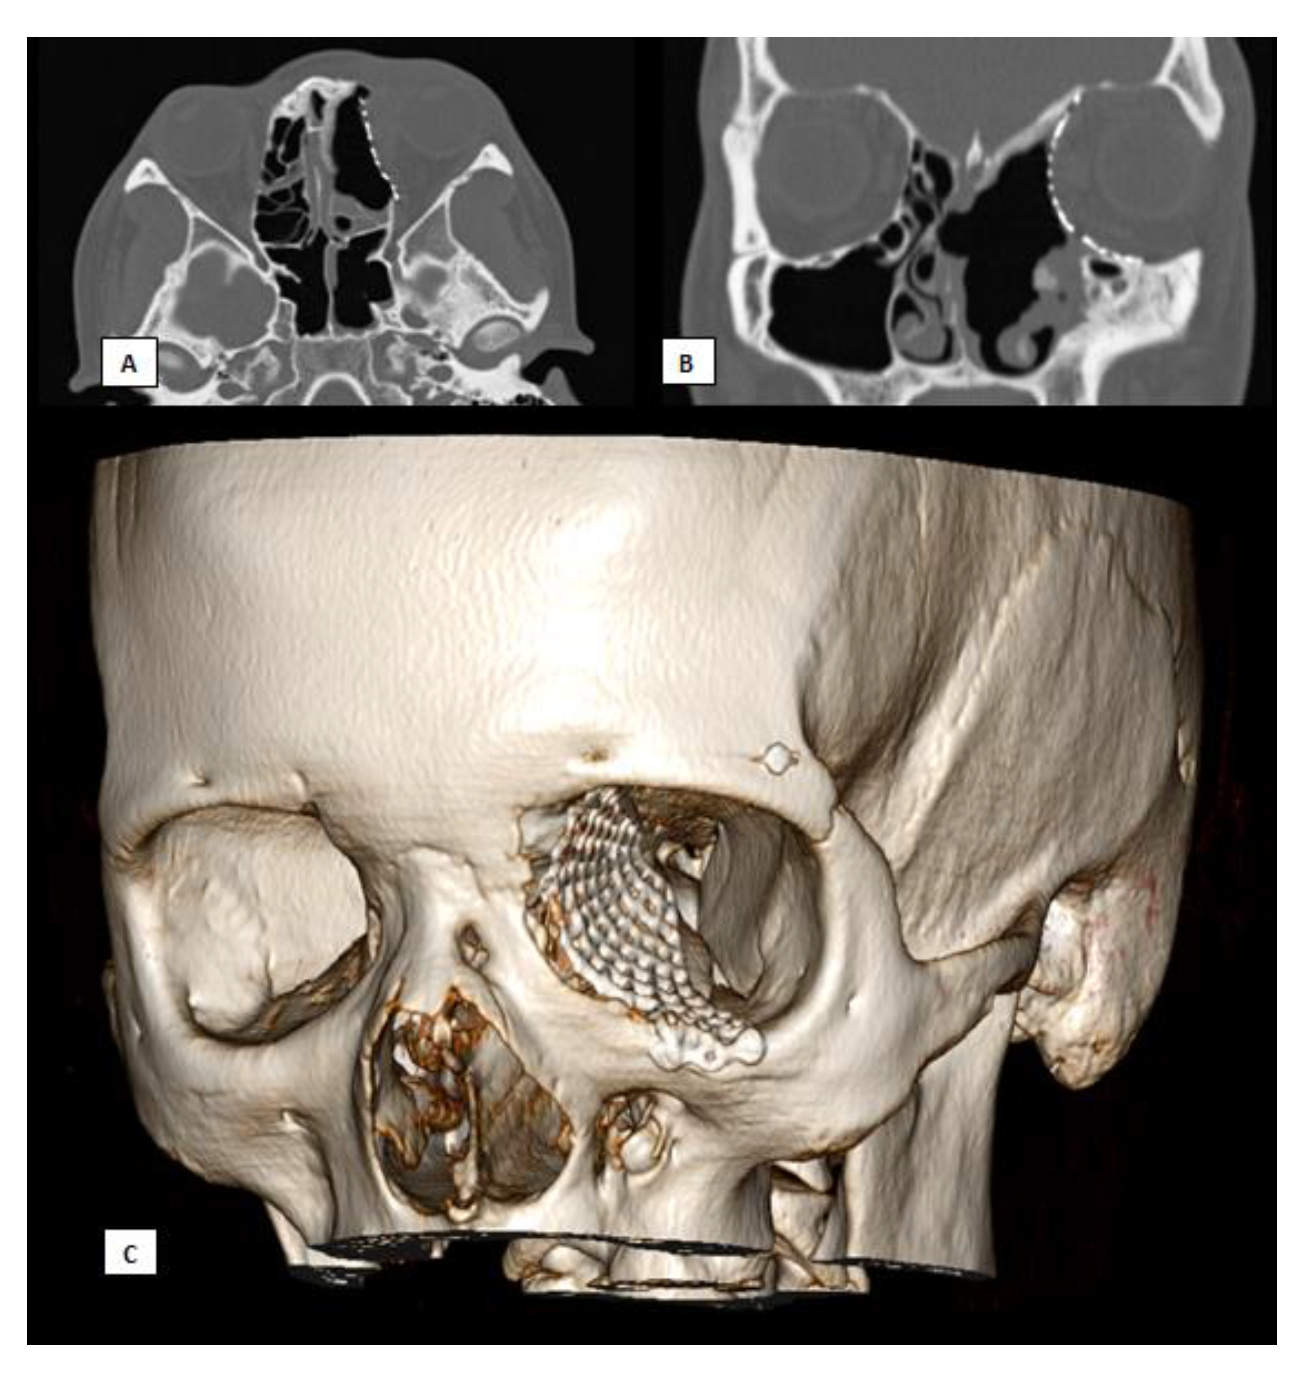

Figure 7.

Postoperative CT scan. (A) Axial view, (B) Coronal view, (C) 3D.

Subsequent follow-up visits over a long-term period of nine years demonstrated excellent aesthetic results, the preservation of extrinsic eye movements, and no neoplasm recurrence.